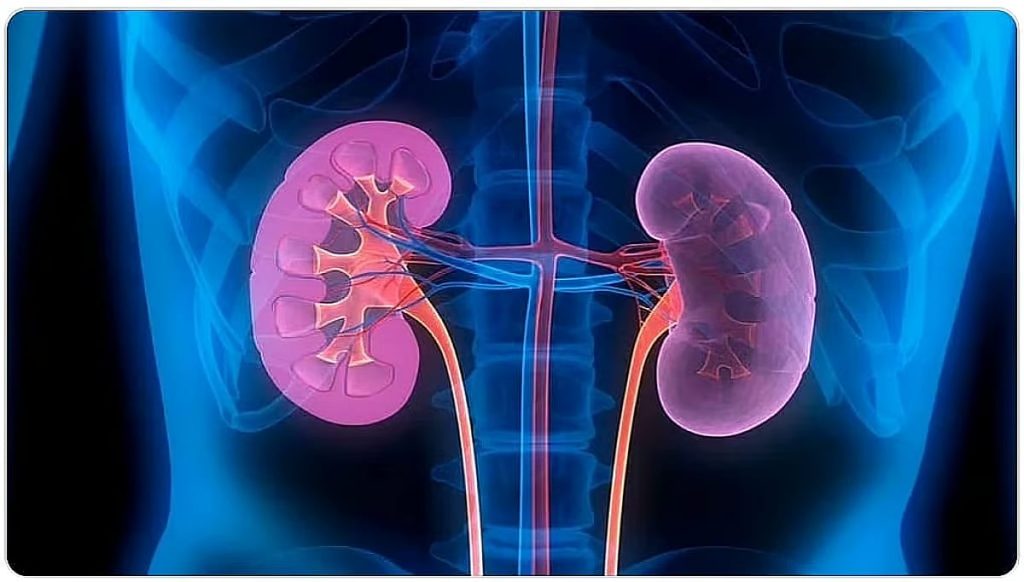

وقالت فهد الطبية في إنفوجراف توضيحي نشرته عبر حسابها الرسمي على منصة “إكس” إن أعراض سرطان الكلى تظهر على هيئة دم في البول، ألم في الظهر أو الجانب، فقدان الشهية ونقص الوزن غبر المبرر بالإضافة إلى شعور بالتعب وارتفاع حرارة الجسم”.

كما بيّنت مدينة الملك فهد الطبية عوامل خطورة الإصابة بسرطان الكلى والتي تشمل التقدم في العمر، السمنة والتدخين بالإضافة إلى ارتفاع ضغط الدم ووجود تاريخ عائلي بالإصابة بسرطان الكلى.

ويمكن علاج سرطان الكلى من خلال الجراحة استئصال كلي أو جزئي أو المعالجة المناعية والمعالجات الدوائية والمعالجة الإشعاعية.

ارتفاع ضغط الدم والتدخين والسمنة من أبرز عوامل الخطورة للإصابة بـ #سرطان_الكلى ، والوقاية تبدأ بنمط حياة صحي#مدينة_الملك_فهد_الطبية#تجمع_الرياض_الصحي_الثاني pic.twitter.com/npTKyXpA6D